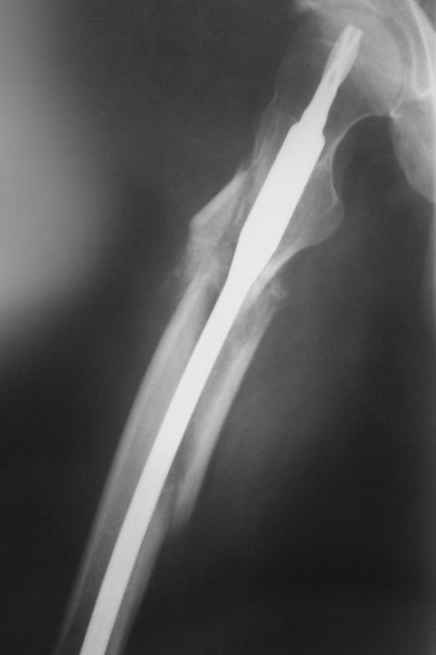

Практически единственное, что делает необходимым разрез для манипуляций с промежуточным отломком бедренной кости - это его "застегивание" в илиотибиальном тракте по типу пуговицы в петле.

Отломок, расположенный так, как на показанных рентгенограммах бедра, обычно на снимках в 1-2 мес. уже располагается ближе к диафизу и

включается в мозоль.